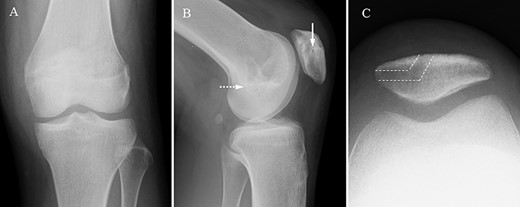

Two months postoperatively, the patient presented with the pain in the medial margin of the patella during walking and knee extension, and the pain continued when she was allowed to start rhythmic gymnastics at 6 months postoperatively. There was no evidence of swelling, crepitus and ROM restriction, and her apprehension sign was also negative. Pain was relieved by an intra-articular xylocaine injection. Postoperative MRI showed no clear injury to the cartilage of the medial PF joint, and the medial PF joint space and the size of the medial plica were almost the same as before surgery (Fig. 2). Based on these findings, left medial plica syndrome was suspected. Although the patient underwent conservative treatment consisting of analgesics and physiotherapy, there were no signs of improvement, and consent was obtained for undergoing arthroscopic surgery at 8 months after the initial surgery. Intraoperative arthroscopic findings with probing confirmed an unenlarged but hardened and thickened medial plica (Fig. 3). No injury to the patellar and femoral cartilage was observed. The synovial plica was considered the main cause of pain, and we performed a partial resection of the medial synovial plica. The pain and the tenderness at the medial margin of the patellar during walking and exercising had gradually improved after surgery. The Lysholm scale improved from 85 to 100 points. At 2 years postoperatively, the patient has currently no pain in the medial side of the patella, negative apprehension sign. She has returned to play in rhythmic gymnastics.

MRI. Axial proton density-weighted (TR = 3000, TE = 12) image before medial patellofemoral ligament (MPFL) reconstruction revealing medial synovial plica (white arrow). The medial patellofemoral joint space and the size of the medial plica after MPFL reconstruction are almost the same as before surgery. There are no clear signs of injury to the cartilage in the patellofemoral joint.